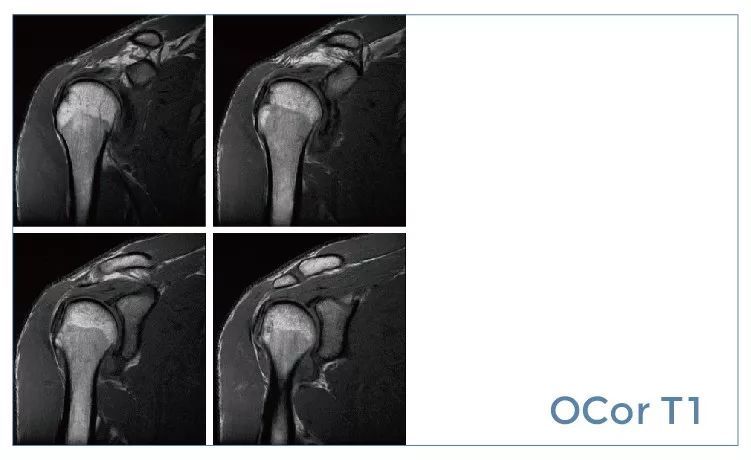

【朗润影像档案】20190927磁共振影像病例结果讨论